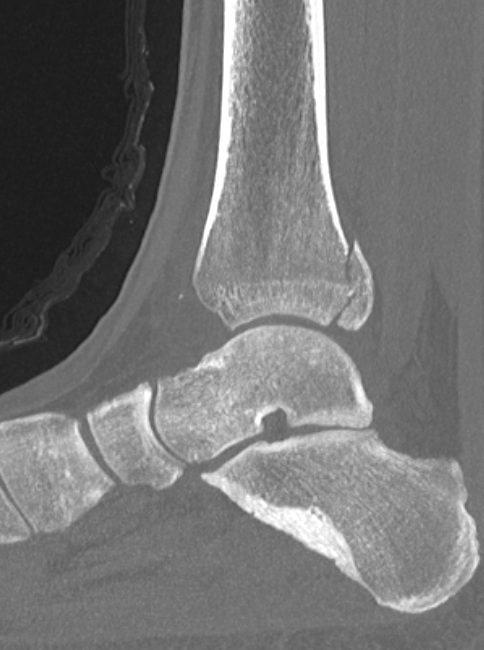

Mason and Malloy Classification

CT scan critical to classify and guide treatment / approach

| Type I | Type IIA | Type IIB | Type III |

|---|---|---|---|

| Avulsion of the PITFL |

Posterolateral fragment Volkmann fracture |

Posteromedial & posterolateral fragments Volkmann plus secondary fracture line |

Large coronal plane fragment Plafond fracture |